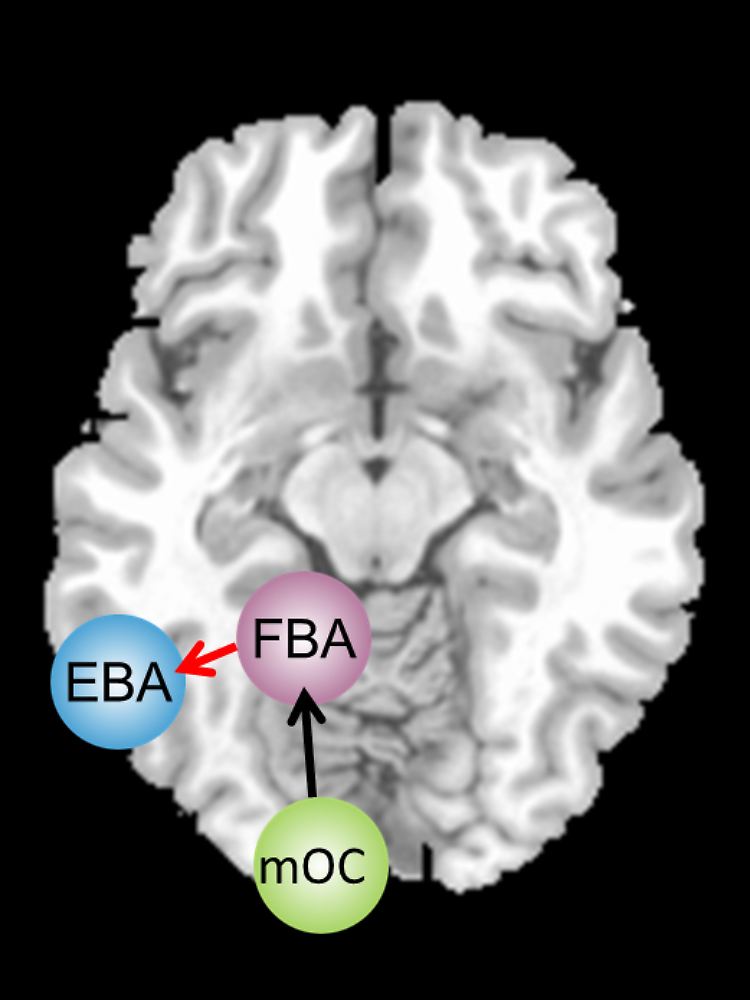

Körperbilder landen als visuelle Informationen zunächst im mittleren Okzipitallappen (mOC). Die „fusiform body area“ (FBA) und die „extrastriate body area“ (EBA) verarbeiten die Bilder anschließend weiter. Bei magersüchtigen Frauen ist die Verbindung vom Areal mOC zur FBA unbeeinträchtigt (schwarzer Pfeil). FBA und EBA arbeiten in der linken Hirnhälfte jedoch nicht normal zusammen (roter Pfeil).

Um diesem Phänomen auf den Grund zu gehen, wurden nun die Gehirnaktivitäten der Probandinnen untersucht, während diese Fotos von verschiedenen Körpern betrachteten. Dabei wurden vor allem zwei Bereiche im Gehirn in den Fokus genommen. Die "fusiform body area", kurz FBA, und die "extrastriate body area", kurz EBA, sind die beiden Bereiche im Gehirn, die für die Wahrnehmung und frühe Verarbeitung von Körperbildern wichtig sind. Dabei konnte eindeutig festgestellt werden, dass das Netzwerk aus FBA und EBA bei den magersüchtigen Probandinnen anders aufgebaut ist als bei den gesunden Frauen.

Die Forscher konnten sogar berechnen, dass die Stärke der Verbindung von FBA zur EBA mit der Körper-Fehleinschätzung der Magersüchtigen parallel geht. Das bedeutet: Je schwächer die Verbindung zwischen FBA und EBA war, umso dicker empfanden sich die magersüchtigen Frauen selbst.